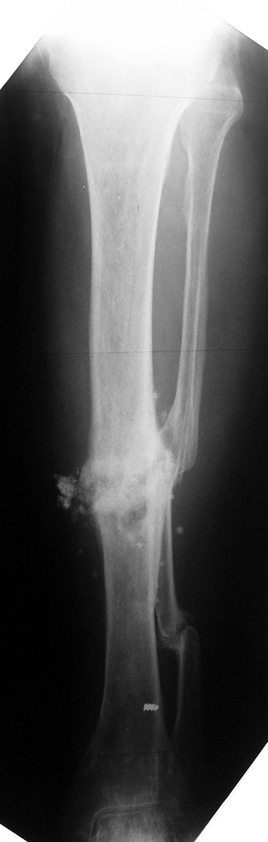

Eksternal fiksatör ile geçen süre (eksternal fiksasyon indeksi), gereken distraksiyon miktarına bağlıdır ve bu süre boyunca bazı komplikasyonlarla karşılaşılabilir. Distraksiyon dönemi sona erdikten sonra, distraksiyon süresinin iki katını aşan konsolidasyon döneminde hastalar eksternal fiksatörü zorlukla tolere edebilirler. Yeterli konsolidasyon sağlanmadan eksternal fiksatör çıkartılırsa ise kırıklar, deformite ve kısalık oluşabilir. Hastanın fiksatör ile birlikte geçirdiği sürenin azaltılması ve böylece hasta konforunun ve aktivite düzeyinin arttırılması için intramedüller çivi üzerinden uzatma yöntemi uygulanmaktadır. Bu yöntemde distraksiyon dönemi sona erdiğinde kemiğin içindeki çivi statik olarak kilitlenmekte ve eksternal fiksatör çıkartılmaktadır. Stabilizasyon intramedüller çivi tarafından sağlandıktan sonra konsolidasyon dönemi gerçekleşmektedir. Bu şekilde hem eksternal fiksatörün uzun süre kalmasından hem de erken çıkartılmasından kaynaklanan komplikasyonların önüne geçilmektedir.